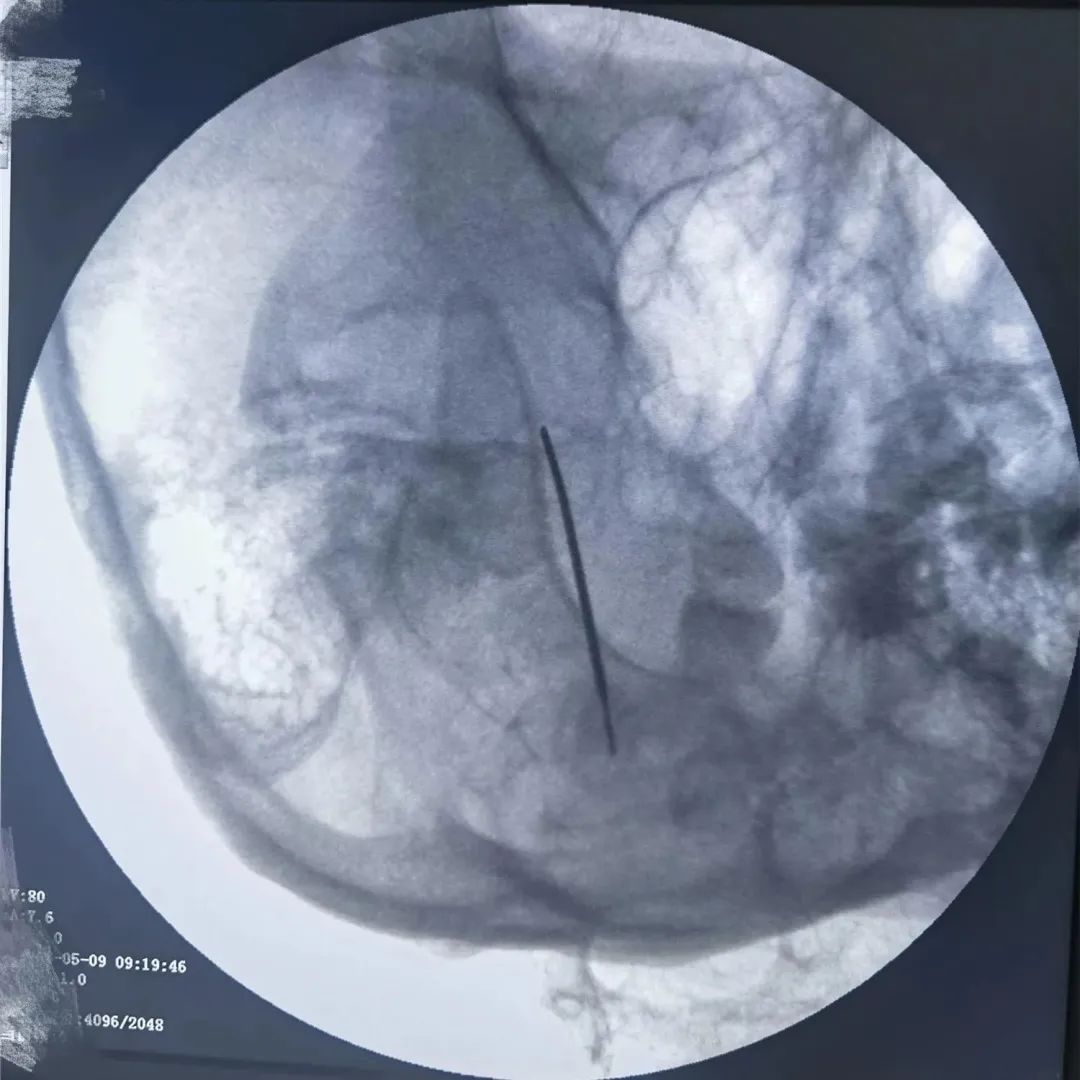

當藥物治療的療效減退或者出現(xiàn)患者無法耐受的藥物不良反應(yīng)而導(dǎo)致藥物治療失敗時,可以盡早考慮外科手術(shù)治療。半月神經(jīng)節(jié)射頻消融術(shù)是近年來隨著疼痛醫(yī)學(xué)的發(fā)展而逐漸發(fā)展并日趨成熟的一門技術(shù),該治療方法成功率高、創(chuàng)傷小,并發(fā)癥少、風(fēng)險小、費用低,是目前治療三叉神經(jīng)痛比較先進且見效快的方法。

經(jīng)過疼痛康復(fù)科李加威副主任詳細問診及相關(guān)檢查后,鑒于患者的病情比較頑固,決定為其進行三叉神經(jīng)痛射頻熱凝術(shù)。治療過程中病人處于清醒狀態(tài),且無明顯不適。治療及康復(fù)過程都很順利,出院時患者未再有發(fā)作性疼痛,精神狀態(tài)明顯好轉(zhuǎn)。